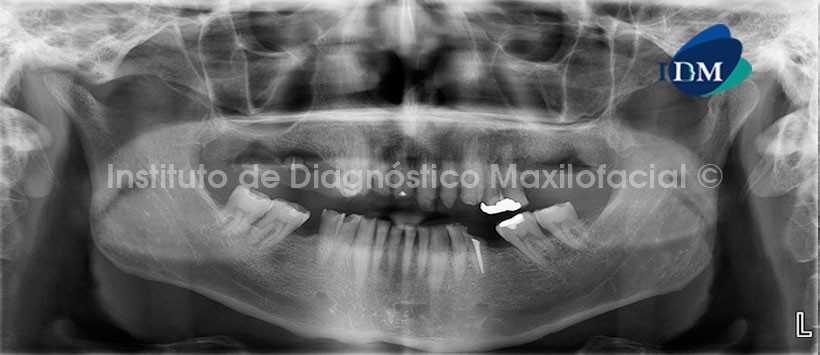

En la evaluación con tomografía volumétrica, en la reconstrucción panorámica (Fig.2) se observa la perdida de estructura dentaria mencionada, así mismo nótese la lesión apical en la pieza 1.1, la misma que en la radiografía panorámica se mostraba discretamente.